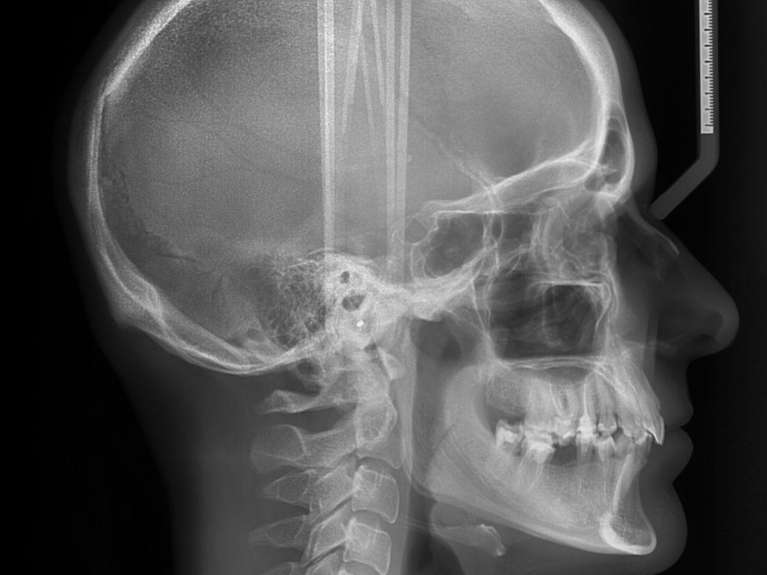

CBCT Cone Beam Technology

With CBCT cone beam technology, we can take our x-rays to the next level. Since your mouth is not two-dimensional, sometimes traditional x-rays aren’t sufficient. With CBCT, we can take a three-dimensional image of your teeth and jaw that can help us plan your treatment for dental implants, impacted teeth or root canal therapy. Don’t worry, though; the CBCT scan only takes a few minutes, and it never touches you when it moves around your head.